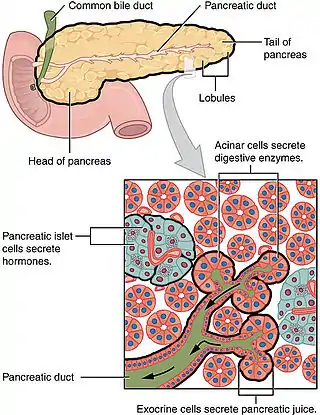

Ductal cells refer to the epithelial cell lining of the pancreatic duct that deliver enzymes from the acinar cells to the duodenum. They have the essential function of producing bicarbonate-rich (HCO3-) secretion to neutralize stomach acidity. The hormone secretin stimulates ductal cells and is responsible for maintaining the duodenal pH and preventing duodenal injury from acidic chyme. Ductal cells mix their production with acinar cells to make up the pancreatic juice.[1]

Ductal cells comprise about 10% of the pancreas by number and about 4% in volume. Its function is to secrete bicarbonate and mucins and to form the tubule network that transfers enzymes made by acinar cells to the duodenum. Ductal cells have a proliferation rate of about 0.5% in normal adults, but mitotic activity goes up when the pancreas is damaged.[3]

The ductal pancreas network originates from the central pancreatic duct—this main duct with the bile duct opens into the duodenum. The ductal cells of the main pancreatic duct are bound by connective tissue and produce a columnar epithelium.[3] Interlobular ducts originate from the main pancreatic duct and connect the various pancreatic lobes. In these lobes, the intercalated ducts expel acini. Meanwhile, the ductal cells of these intercalated ducts create a simple squamous epithelium that rapidly converts into simple cuboidal, and connective tissue also surrounds them.[3] As the ducts grow larger, the epithelium becomes cuboidal or columnar (when large in diameter, the ducts become stratified cuboidal), and connective tissue surrounds them. Pancreatic ductal cells are very similar to ductal cells of other exocrine glands (liver, bile duct, salivary glands).[3] Because of this, a common diagnosis affects these cells: cystic fibrosis.

While ductal cells are a minor type of cell in the adult pancreas, they have a critical function besides making the network that transfers enzymes from acini to the digestive tract. The primary function of pancreas ductal cells is to secrete a bicarbonate-rich, isotonic fluid. This fluid washes away the inactive form of digestive enzymes in the ductal system, neutralizes stomach acidity and mucins, and creates a pH environment necessary for the pancreas's normal function.[4]

The largest network branches in this system contain goblet cells that interact with ductal cells, making up about 2% of this structure—these cells aid mucin assembly. Furthermore, unlike other exocrine glands, the pancreas does not have myoepithelial cells around the ducts.[3] Ductal cells have a single cilium that is made up of nine peripheral doublets but does not have a central microtubule. This cilium is considered vital for perceiving flow in ducts.[3]

Morphology is what identifies ductal cells. However, there is barely anything to differentiate pancreatic ductal cells from other bodily ductal cells.[6] There is still a lot unknown about these ductal cells. Their molecular identity still needs to be improved; more knowledge is necessary regarding stage-specific markers and the regulators of ductal cell development. It recently was discovered that the ducts start as separate microlumens in a stratified epithelium that expand, attach, and resolve to form the pancreatic ducts. These cells work with intercalating ducts that link to distinct acini and are within the larger ducts in the two core pancreatic ducts (dorsal and ventral duct) that drain into the intestine.[6]